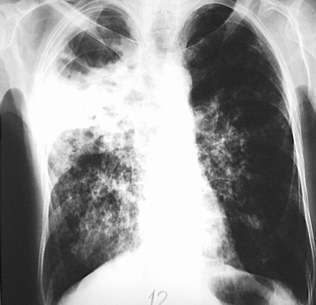

Hình ảnh X quang một lao phổi